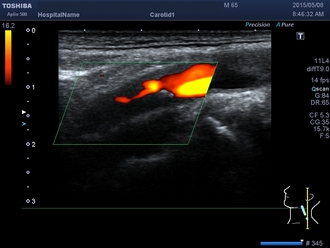

頸動脈超音波検査

頸動脈の動脈硬化度は、全身の血管の動脈硬化を反映しているといわれております。したがって、早期動脈硬化のチェックから何らかの血管病変のある方まで幅広く行われております。

☆写真の説明☆動脈硬化が進行し、内頸動脈(脳へ血液を送る血管)がつまっていることがよくわかります。色の付いているところが血液が流れているところで、その流れが細くなって途絶えています。 |